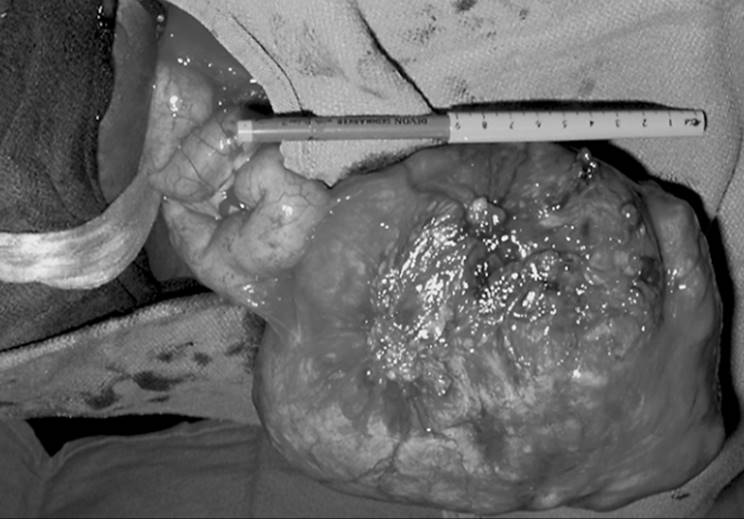

When symptomatic leiomyomata are not completely within the endometrial cavity but in an intramural location, an abdominal surgical approach usually is required. With infrequent exceptions, a low transverse incision yields adequate surgical exposure. Rarely, a vaginal myomectomy can be performed with proper patient selection, but this clinical situation is rare and requires a high degree of surgical skill. The goal of a myomectomy is to remove all the identifiable leiomyomata with the least possible alteration of the reproductive tract. There are numerous surgical techniques but, in general, the myometrium is incised, the myoma dissected from the surrounding myometrium, and the incision closed in layers with absorbable suture to ensure hemostasis and myometrial integrity (Fig. 49.5). Entry into the endometrial cavity is not associated with any significant morbidity, but it is essential not to place sutures though the endometrial cavity wall as if it is a layer to close. Because the distance to the opposite endometrial surface is small, approximating the myometrium underlying the endometrium to the corresponding opposite side is all that is necessary. Cervical fibroids can represent a significant surgical challenge because of their proximity to the bladder and ureters, as well as the difficulty attaining hemostasis. Similarly, parasitic fibroids can be difficult to remove depending on their vascular supply (Fig. 49.6).

FIG. 49.6. A parasitic fibroid. A large tumor has become parasitic to a loop of small bowel, deriving its blood supply from the new vascular source. This typically happens only with large posterior or fundal tumors and is more common when they are pedunculated. The mechanism is felt to be pressure necrosis and revascularization during healing of the necrosis of the bowel wall.